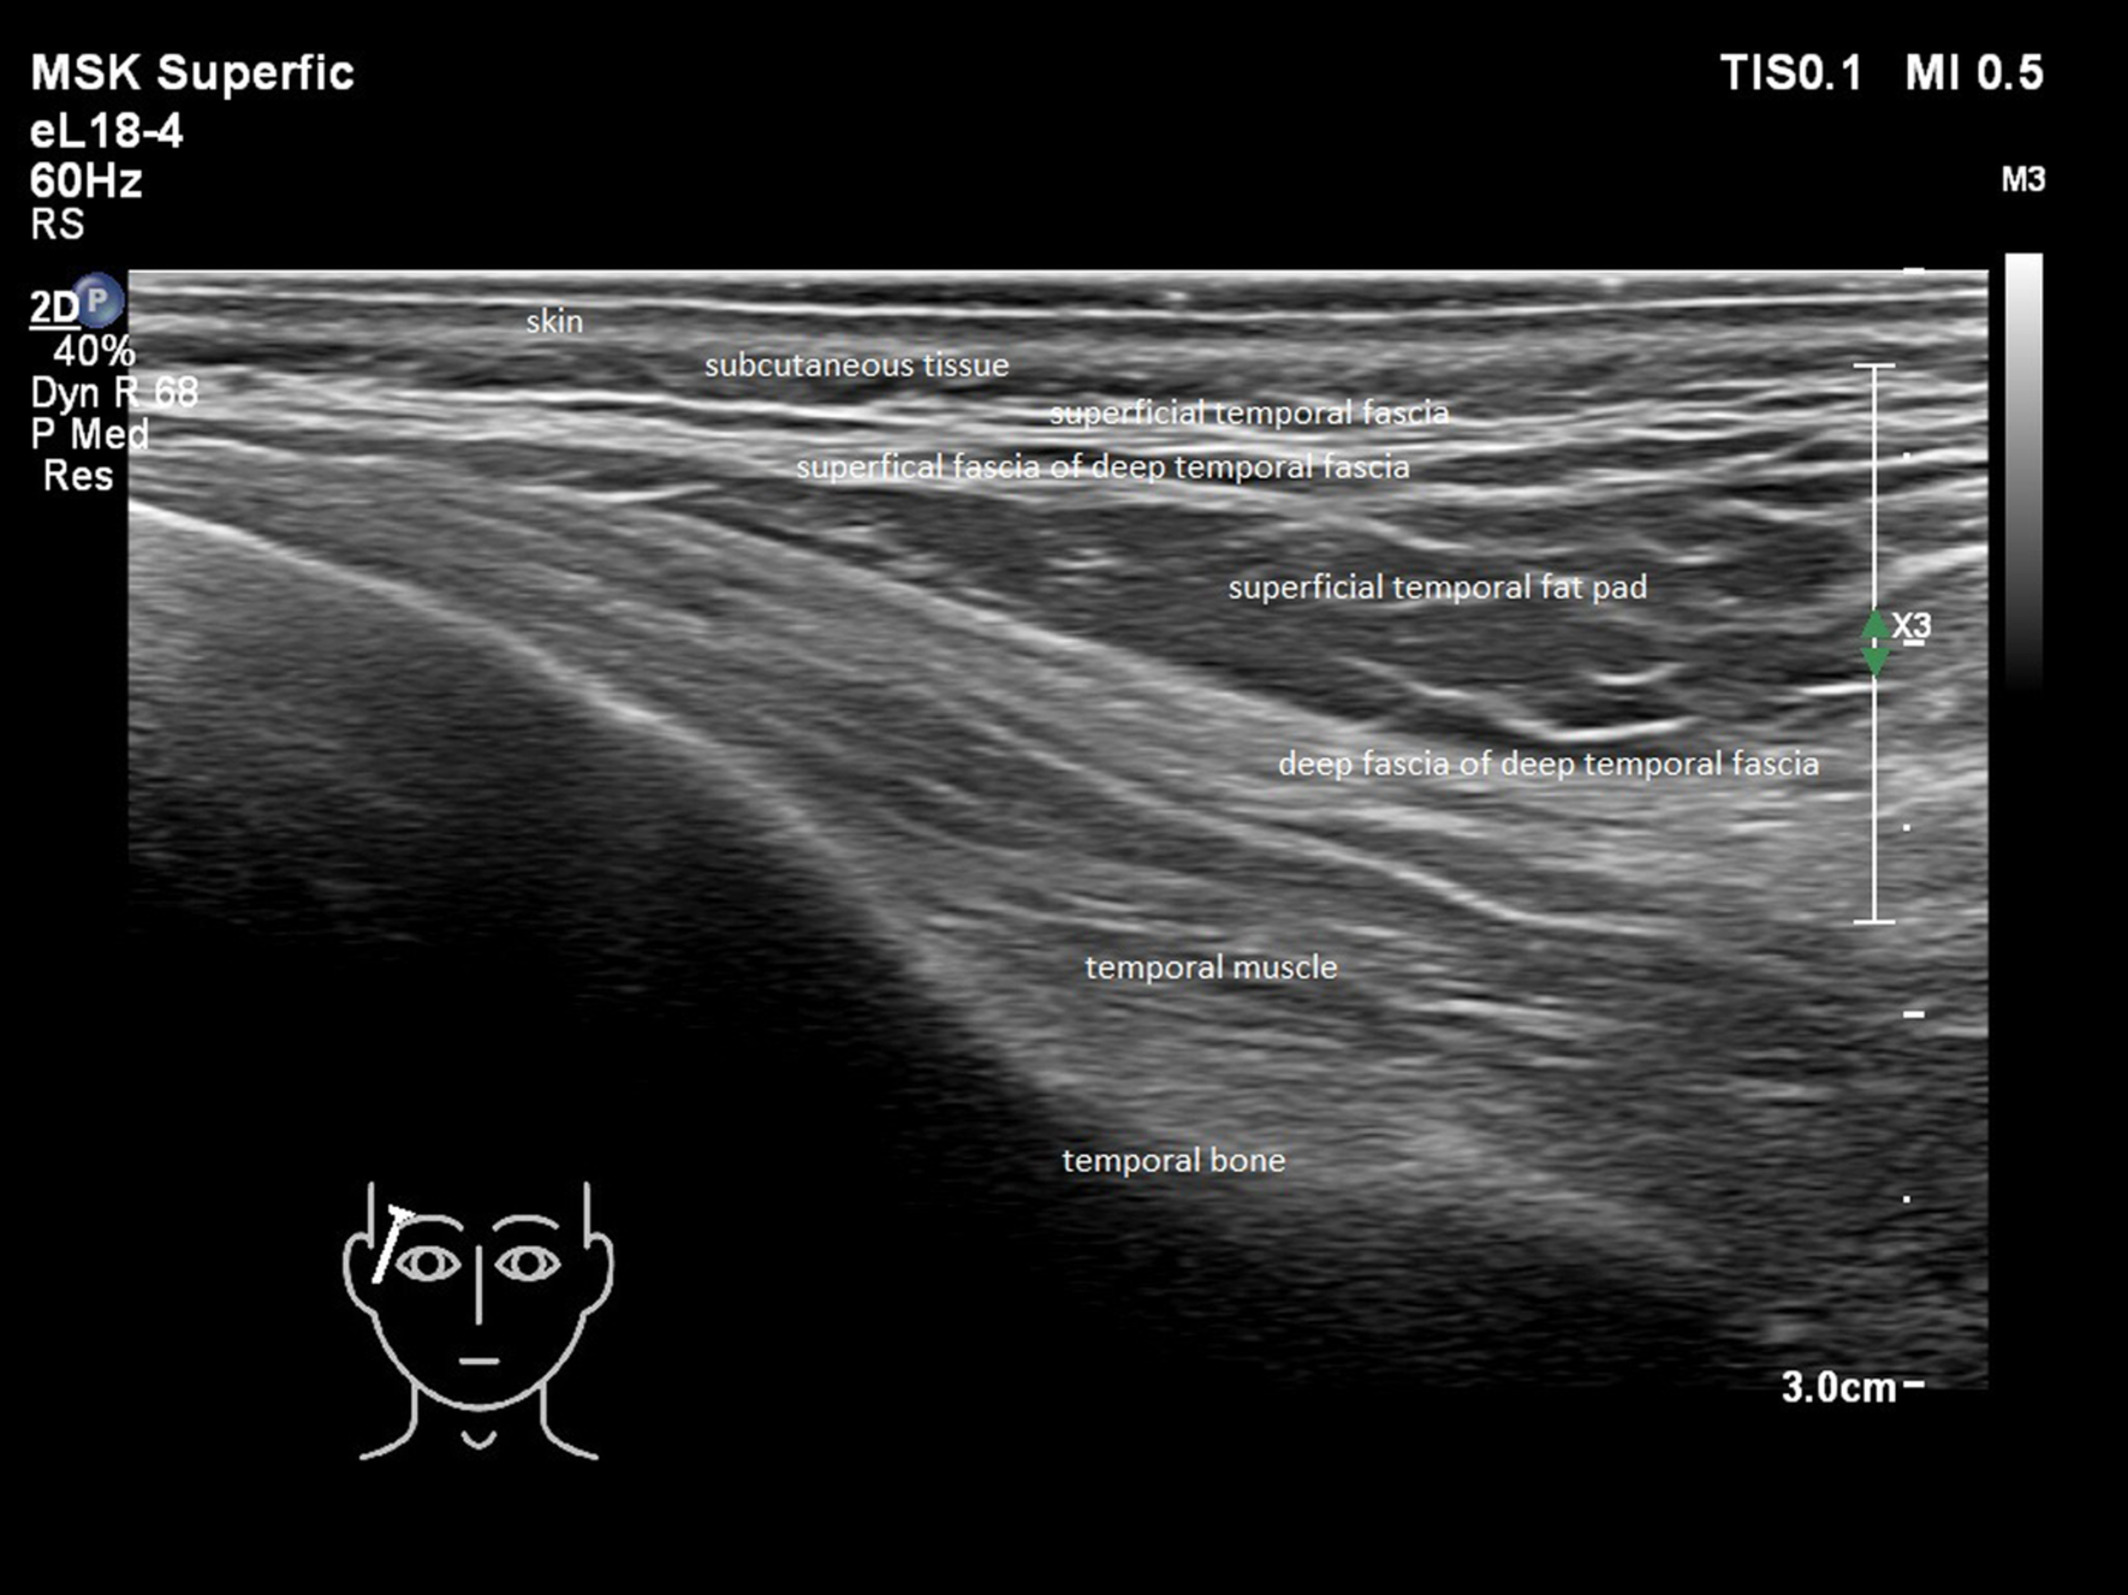

Figure 2. See attachment of picture. The temple is a potential high risk area for injections. In this picture, layers of the temple are visualized by US 18MHz.